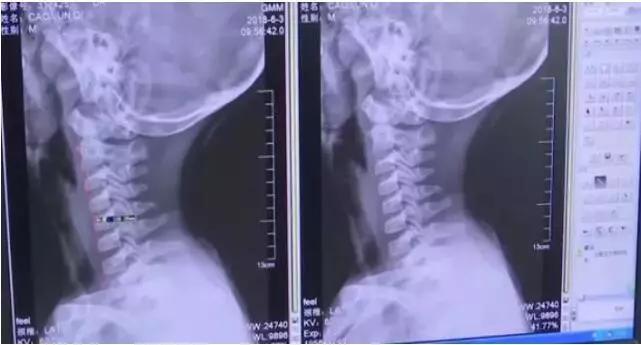

经过CT检查发现,男孩的颈椎出了问题。正常的颈椎是带有前曲弧度的,可男孩的颈椎生理曲度消失,竟然变直了!听到这个结果的时候,家长都震惊了。

一般颈椎问题不是都出现在中年和老年人身上吗?孩子才9岁,怎么会出现这种问题?

在医生和家长的沟通下,才知道,原来这名男童一年多来,经常长时间低头玩手机。

长期低头,加上姿势不正确,才给颈椎造成了过重的压力。

医生解释说:低头看手机,颈椎所承受的重量是垂直时的3倍,如果姿势不当,可能让颈椎承受多达27公斤的重量!长期以往,颈椎很容易就出现问题。(新闻来源:南通头条 2018.06.13 )